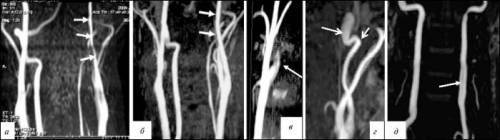

Механизм диссекции означает разрыв внутренней оболочки артерии и проникновение крови между слоями стенки. Подобный процесс обнаруживают в области ответвления внутренней сонной артерии. Сформированная внутристеночная гематома образует препятствие потоку крови.

Признаки диссекции выявляются при магниторезонансной ангиографии

Итогом перечисленных механизмов всегда является сужение (стенозирование) диаметра артерии. В результате головной мозг недополучает кислород, развивается клиническая картина гипоксии тканей, ишемического инсульта.

Как образуется и проявляется извитость сонной артерии?

Обнаружить извитость стало возможным с развитием методов исследования сосудов (ангиографии, ангиотомографии, допплерографии). Причины образования этой патологии до настоящего времени неясны, хотя распространенность достигает 25% всего населения.

Наиболее понятными объяснениями считаются:

- врожденные изменения;

- последствия повышенной нагрузки на артерии при гипертензии, атеросклерозе.

В любом случае сосуд становится более длинным и вынужден принимать разные формы:

- мягкие изгибы и повороты под тупым углом — чаще обнаруживаются случайно и не имеют клинической симптоматики до тех пор, пока не образуются выраженные загибы, способные пережать основной сосуд;

- кинкинг — артерия своим направлением образует острый угол;

- койлинг — сосуд имеет форму петли, кровоток значительно замедляется, есть симптомы ишемии мозга.

Последние две формы лечатся только хирургическим путем.